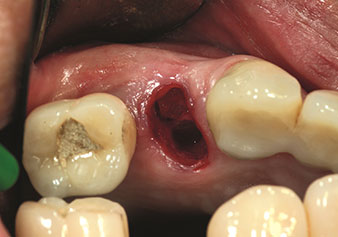

One application, which is often underestimated is the atraumatic extraction of tooth roots or root fragments in the scope of alveolar management. The fine periotomes, which are currently available in two versions (EX1 and EX2 from W&H), can also be used to remove teeth which have previously undergone special endodontic treatment or ankylosed roots with ease. This results in extraction alveoli where both the hard and soft tissue are fully intact as it is generally possible to avoid reflection.

This establishes the optimal basis for subsequent or immediate implant treatment (Figures 1 and 2 included with the kind permission of Dr Torsten Conrad, Bingen a. Rhein).

Situation following piezosurgical extraction

Fig. 2: Situation following piezosurgical extraction.

Photo: © Dr Torsten Conrad (Bingen am Rhein)